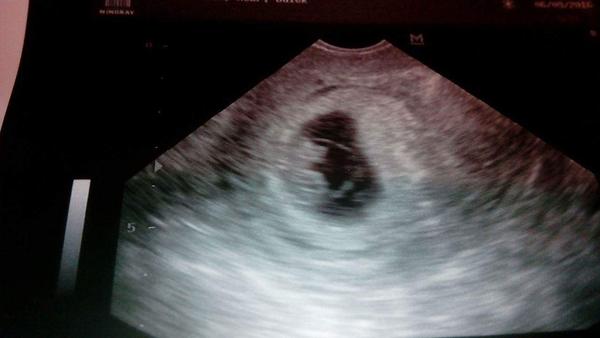

Ahoj holky, tak vkládám foto, které jste si "vyžádaly" odpovídáme 8+1. Pry od minula povyrostlo a uz ma pidi pahylky na nohy 😁

@cherry09 jeziiiis💜 hodne stesticka preju, doufam ze pristi tyden uz taky ukazu fotecku, nebo aspon at tomu prckovi krasne bije srdicko💜😊

@cherry09 jee 😍😍 tak at krasne rostete 🙂

@cherry09 jeee, dobre zpravy a pekna fotecka 😃to uz bilo i srdicko vid. Krasa 😍